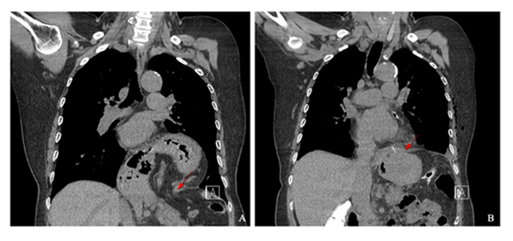

The most common presenting symptom was gastrointestinal discomfort (5/11, 45.5%), followed by chest pain (2/11, 18.2%), respiratory distress (2/11, 18.2%), and back pain (2/11, 18.2%); three patients (27.3%) were asymptomatic at diagnosis (Table 2). Computed tomography (CT) established the preoperative diagnosis in all patients, and routine postoperative CT was obtained on postoperative day (POD) 5 (POD 6 for the Bochdalek case) (Figures 4-6).

- Hiatal hernia; Pre-OP CT

- Post-OP CT (POD #5)

- Morgagni hernia ; Pre-OP CT

- Post-OP CT (POD#5)